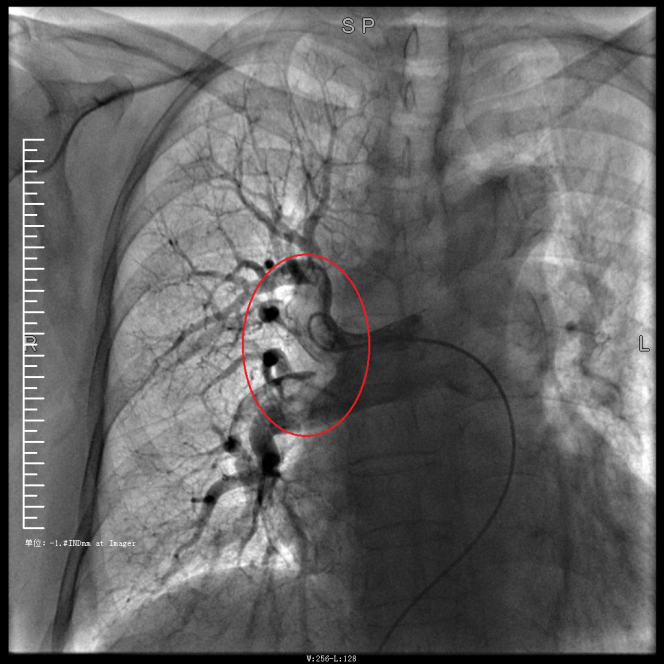

譚婆婆今年已經(jīng)72歲了,因“突發(fā)意識障礙2次”到璧山區(qū)人民醫(yī)院神經(jīng)內(nèi)科治療。譚婆婆沒有基礎(chǔ)心臟病病史,但近段時間活動耐量明顯下降,稍做活動就出現(xiàn)呼吸困難。入院后查BNP及心臟彩超均未提示明顯異常,查D二聚體明顯升高,經(jīng)心血管內(nèi)科周波醫(yī)師會診后轉(zhuǎn)入科室繼續(xù)治療。在心血管內(nèi)科主任、內(nèi)科學(xué)(心血管病)博士于長青的指導(dǎo)下,周波醫(yī)師成功完成醫(yī)院首例“一站式”微創(chuàng)介入手術(shù)。在影像中,可以清晰地看到堵塞的血管經(jīng)溶栓治療后,重新暢通無阻,流動起支撐生命的血液。

肺動脈造影技術(shù)是目前診斷肺動脈栓塞的“金標(biāo)準(zhǔn)”,在全程心電監(jiān)護下,通過股靜脈或者頸內(nèi)靜脈置入鞘管后,利用導(dǎo)絲引導(dǎo),將造影導(dǎo)管送入肺動脈;可在左/右肺動脈主干及其左右分支內(nèi),分別進行肺動脈造影或選擇性肺動脈造影,存在栓塞的肺動脈血管在造影劑注入后即會顯示出充盈缺損、充盈緩慢、或者血管顯影模糊,嚴重栓塞的肺動脈血管甚至?xí)霈F(xiàn)血流截斷征象。

肺動脈導(dǎo)管局部置管溶栓術(shù)是通過肺動脈造影確定堵塞的肺動脈部位,然后導(dǎo)管尖端置于血栓處,將尿激酶、鏈激酶或重組組織型纖維蛋白溶酶原激活劑直接注入血栓處,新鮮血栓在足量的溶栓劑作用下溶解。肺動脈內(nèi)局部用藥特別是小劑量時可減少出血并發(fā)癥。

注明:第一張、第二張為術(shù)前圖像